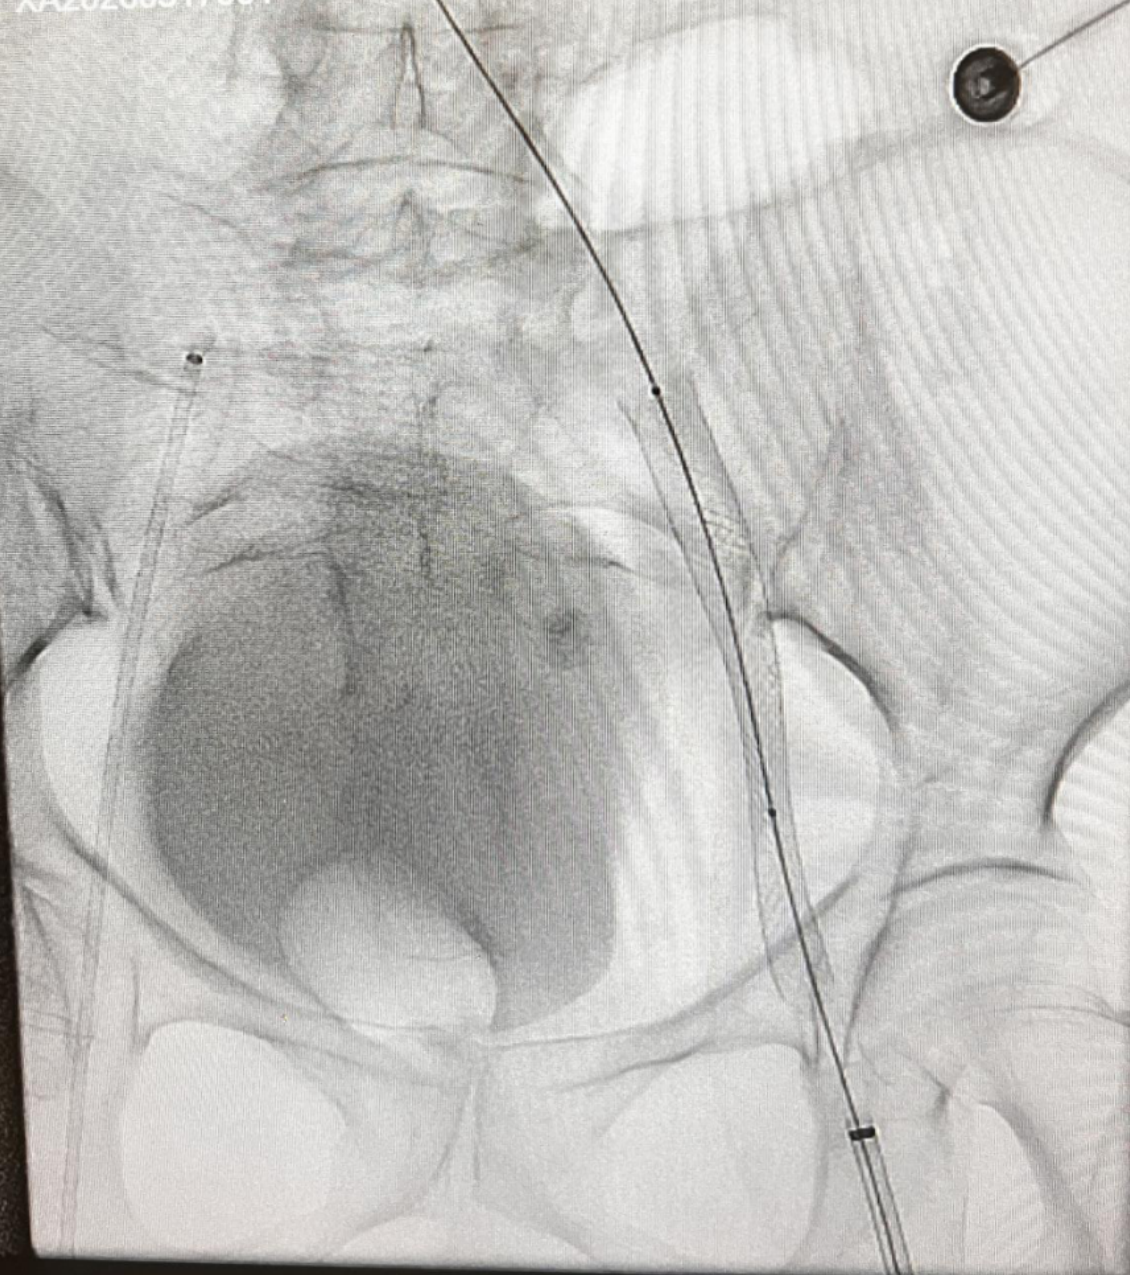

(图4:球囊扩张(PTA)术后影像,示闭塞血管开通成功、血流恢复)

整台手术操作顺利,术中、术后患者生命体征平稳,血栓清除效果理想,患肢血流即刻恢复,下肢肿胀症状明显减轻。术后医院对患者予以规范抗凝治疗及严密病情监护,患者恢复进程顺利,各项临床指标趋于正常。